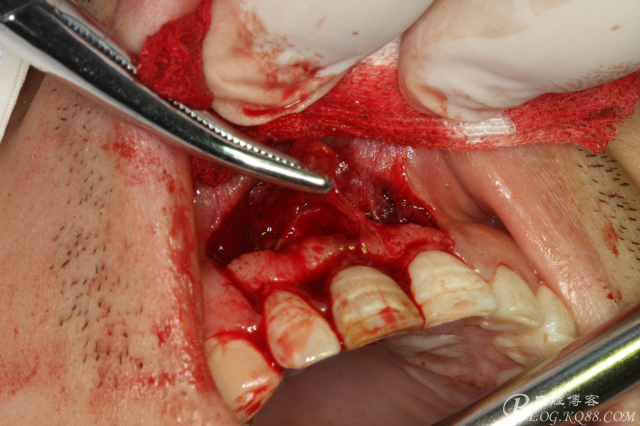

圖8. 觸目驚心發(fā)現(xiàn)11唇側(cè)骨壁完全缺失,根充超填。預(yù)后難以判斷。